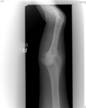

Congenital radiial hypoplasia

21 year old male treated previiously elswhere many years ago with centralisation of the ulna and multiple sof tissue procedures

Presented with recurrence of deformity and fused wrist

Pre

Op

Xrays